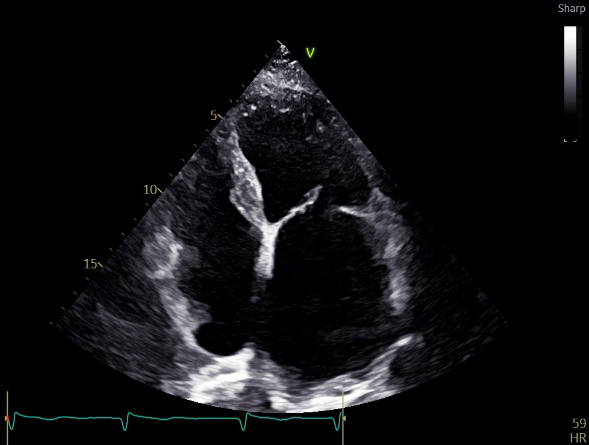

术前超声评估

术前超声诊断

LVOT-color:MR(重度),返流面积11.3cm2

肺静脉血流频谱呈收缩期反向

3D-color MV view:血流主要来源于2、3区

Qlab软件勾画估测瓣口面积约:6.16cm2

TEE LVOT切面返流量评估

TEE 4-Ch view返流量评估